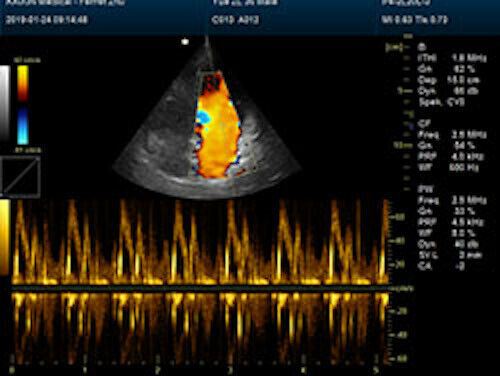

Large Animal Veterinary Color Doppler Ultrasound & Rectal Probe

| Rich clinical application function • B+CF (Dual Images) • B+CF/PDI/DPDI+PW (Triplex) • Convex extended imaging technology • Linear array deflection/Trapezoidal imaging technology • Spatial compound Imaging technology • Panoramic imaging technology (optional) • 3D/4D imaging technology (optional) • Speckle noise removal technology • Pulse inversion tissue harmonic imaging technology (iTHI) |